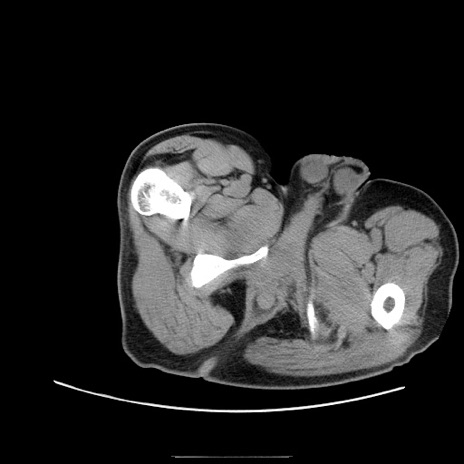

症例22(横断像)

冠状断像

【症例】50歳代男性

【主訴】腹痛

【現病歴】AVMからの被殻出血のため回復期リハ病棟入院中。 本日午後3時頃急に下腹部痛が出現した。

【既往歴】AVM、被殻出血、虫垂炎、高血圧

【身体所見】意識晴明、左半身不全麻痺、会話の理解は良好、36.5°C、腹部:膨隆、全体に板状硬、下腹部正中に圧痛点あり、反跳痛-、筋性防御不明、右下腹部にope scar

【データ】WBC 9400、CRP 0.06